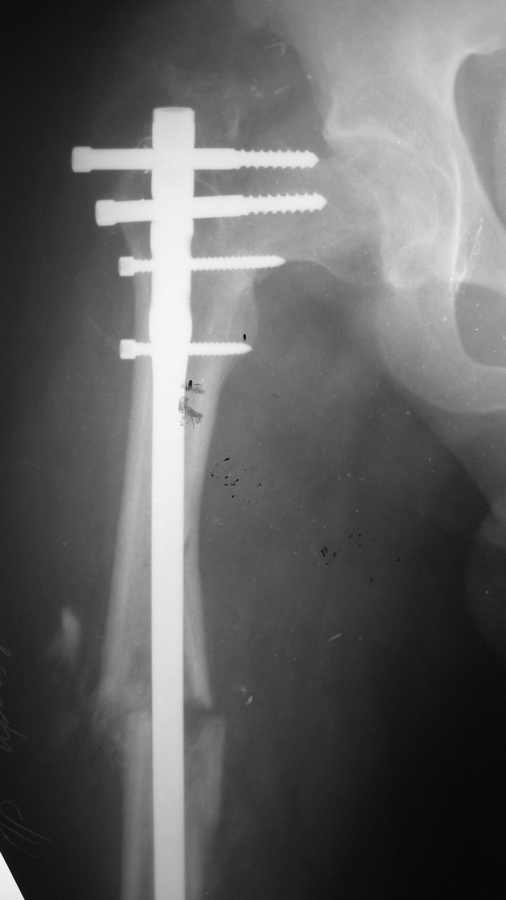

Парень, 23 года, исходно здоров.25 октября 2008 вследствие ДТП политравма (мотоциклист): оскольчатый диафизарный перелом правой бедренной кости + чрезвертельный перелом правого бедра ( был диагностирован во время операции, был без смещения). Перелом двух лодыжек и перелом пятки слева. По скорой помощи через 6 часов после аварии произведено оперативное лечение: интрамедулллярный остеосинтез правого бедра + фиксация чрезвертельного перелома 3-мя винтами. Металлоостеосинтез голеностопного сустава слева, пятка не оперировалась.После операции через 14 часов развилась жировая эмболия легких, тяжелая форма, которая разрешилась благополучно.При контрольной рентгенографии через 1 месяц отмечено смещение в области чрезвертельного перелома,варусная деформация.Сейчас прошло 6 мес. Идет медленная консолидация переломов. Необходима реконструктивная операция.Вопрос: какая (метод?), когда, ведущие клиники. Общее состояние сейчас удовлетворительное, жалоб нет.

Длинная версия PFNa

Этот гвоздь, как и гамма, PFN, IMHS, ATN, Intertan и т.д. и т.п., будучи введены в правильном положении отломков, способны удержать и проксимальный отдел бедра, и диафиз. А здесь, очевидно, проблема в том, что этому предшествует - как восстановить форму проксимального отдела бедра и сохранить ее до запирания гвоздя?

Спасибо за ответ. Мы думаем о PFN, DHS, но мы боимся развития аваскулярного некроза шейки бедра (AVN) + в анамнезе все же тяжелая жировая эмболия. Склоняемся к корригирующей остеотомии. Ваше мнение?

Есть предложение наложить дистрактор, удалить данный гвоздь и провести его ретроградно ( если это Chm)а проксимальный отдел фиксировать DHS.

Нужно удалить стержень! Взять стержень большего диаметра (min 12 мм), предварительно расверлив канал, и синтезировать по реконструктивному типу в шейку бедренной кости. Предварительно отрепонировав переломы. Совет из собственного опыта...

А для DHS и PFN слишком молодой возраст, так как обе конструкции через 5-6 лет приводят к асептическому некрозу. Ретроградный же метод введения стержня в данном случае не подходит, так как приводит в отдаленных результатах к артрозу коленного сустава.